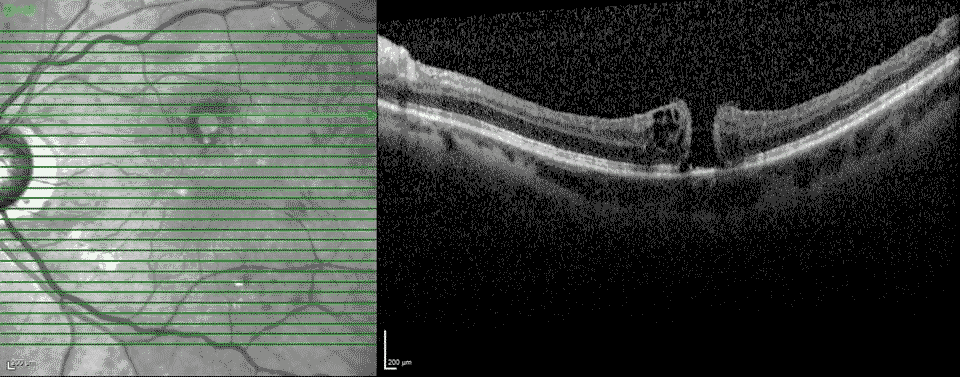

Fig 3-8: OCT OS: scant ERM remnants nasal to the fovea; thinning temporal in areas of prior membrane peeling.